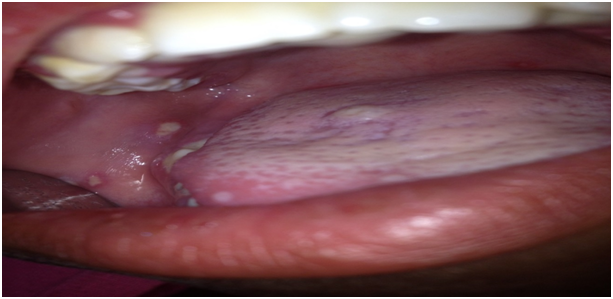

A nine year old, female presented with a main complaint of difficulty eating due to pain associated with multiple shallow oval oral ulcers. The patient’s mother said her daughter complained of pain 3 days ago and she started eating less due to pain and a gradual lack of appetite. She experienced constant pain in the entire mouth without any burning sensation. The pain became more pronounced when she was eating and had difficulty swallowing. On extra oral examination enlarged submandibular lymph nodes were palpable both on left and right side which were mobile, tender and soft in consistency. Patient appeared weak and dehydrated and had a fever. Her speech was slurred and she had no known allergies and she was HIV negative. On intra oral examination she had an erythematous area surrounding the inner border of the upper and the lower labial mucosa (Figure 1). The marginal and attached gingiva was swollen and inflamed, the gingiva formed tissue tags over the lower primary canines (73 and 83) characterized by erythema, oedema, capillary proliferation (Figure 2). Multiple shallow ulcers measuring less than 0.5cm were present on the floor of the mouth, tongue lateral borders, the buccal, labial and gingival mucosa which were surrounded by an erythematous area (Figures 3 & 4). Patient had no oozing from any of the ulcers however they were extremely painful on swallowing or talking. The patient had severe halitosis and a high salivary flow and her teeth had a severe build-up of in plaque and calculus deposits. The lower posterior molars (74, 75, 84 and 85) had tooth decay however the teeth were asymptomatic.

Figure 3: Ulcers on the buccal mucosa and lateral border of the tongue.

Figure 4: Multiple ulcers on lower gingival mucosa and floor of the mouth.